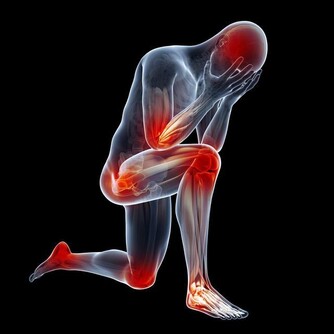

人體的正常活動離不開水的參與,離開了水,身體各項機能也就無法正常運轉。水多了就要參與代謝,最終形成尿液流出體外。尿液量的多少,也就和喝水量有關係。正常人的飲水量在1500到1700毫升之間,尿液量也就在1300到1500左右。在每一次喝水後的2個小時之內,基本都會有尿意出現。偏偏就有人不遵循這樣的規律,不是一喝水就有尿意,就是喝多了也沒有尿意出現,到底是什麼原因?

有沒有可能是身體方面的原因呢?自然是可能的。畢竟尿液是經過過濾形成的,尿液來得過快自然不能排除是這方面的因素。不過,一般不會是單純地喝水後就想尿,還會伴隨著其他方面的問題,諸如夜尿次數增多、尿液渾濁之等等。

喝水多沒有尿意,一般認為是少尿或者是無尿的情況。無論是哪一種情況,都和是否喝水,喝水多少並沒有關係,主要是看尿液總量。每天的尿液總量,不到400毫升屬於少尿,不到100毫升屬於無尿。這些情況的出現,和飲水量以及出汗量有關係,飲水少、出汗多的人往往會出現少量的情況,在一些熱衷於運動的人身上比較常見。除去這種生理性因素之外,一樣可能是身體方面的問題。當它的過濾能力逐漸下降時,尿液的形成過程也就出現了問題,尿液量會顯著減少,同樣是不容忽視的。